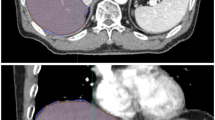

As shown in Figure1, the GTV on APCE 3D CT scan identified a clear edge and the boundary of the GTV could be easily determined. In contrast, the boundary was blurred on NCE 4D CT and 3D CT images. The average GTV from APCE and NCE 3D CT scans was 20.92±13.20 cm3 and 15.52A comparison of GTVs obtained from 3D and 4D CT scans in different breathing phas11.86 cm3 respectively and 15.13±12.04 cm3 for NCE 4D CT scans. The GTV volume was 34.79% higher in APCE 3D CT image than in NCE 3D CT image (P < 0.05). No significant differences were found among the GTVs obtained using NCE 3D and 4D CT scans (P > 0.05), as shown in Table1.

After DR, the volumes of GTVs obtained from 4D CT images increased by an average of 20.62±12.73 cm3, a 36.29% increase from the value obtained before DR (P < 0.05). The mean GTV after DR did not vary significantly from the value obtained from the APCE 3D CT image (P > 0.05), as shown in Table1 and Figure2.

The image registration transformation vectors that were used to register the APCE 3D CT image to CT00 phase of 4D CT images are shown in Figure4. The vector fields on the axial, coronal and sagittal slices are marked according to the legend. Ideally, the deformed CT00 phase image would be identical to the 3D CT image. In practice, it was similar but not identical due to imaging artifacts and spatial resolution inaccuracies. Inspection of the deformed regions suggests good agreement of the tumor and liver after DR, as shown in Figure2.